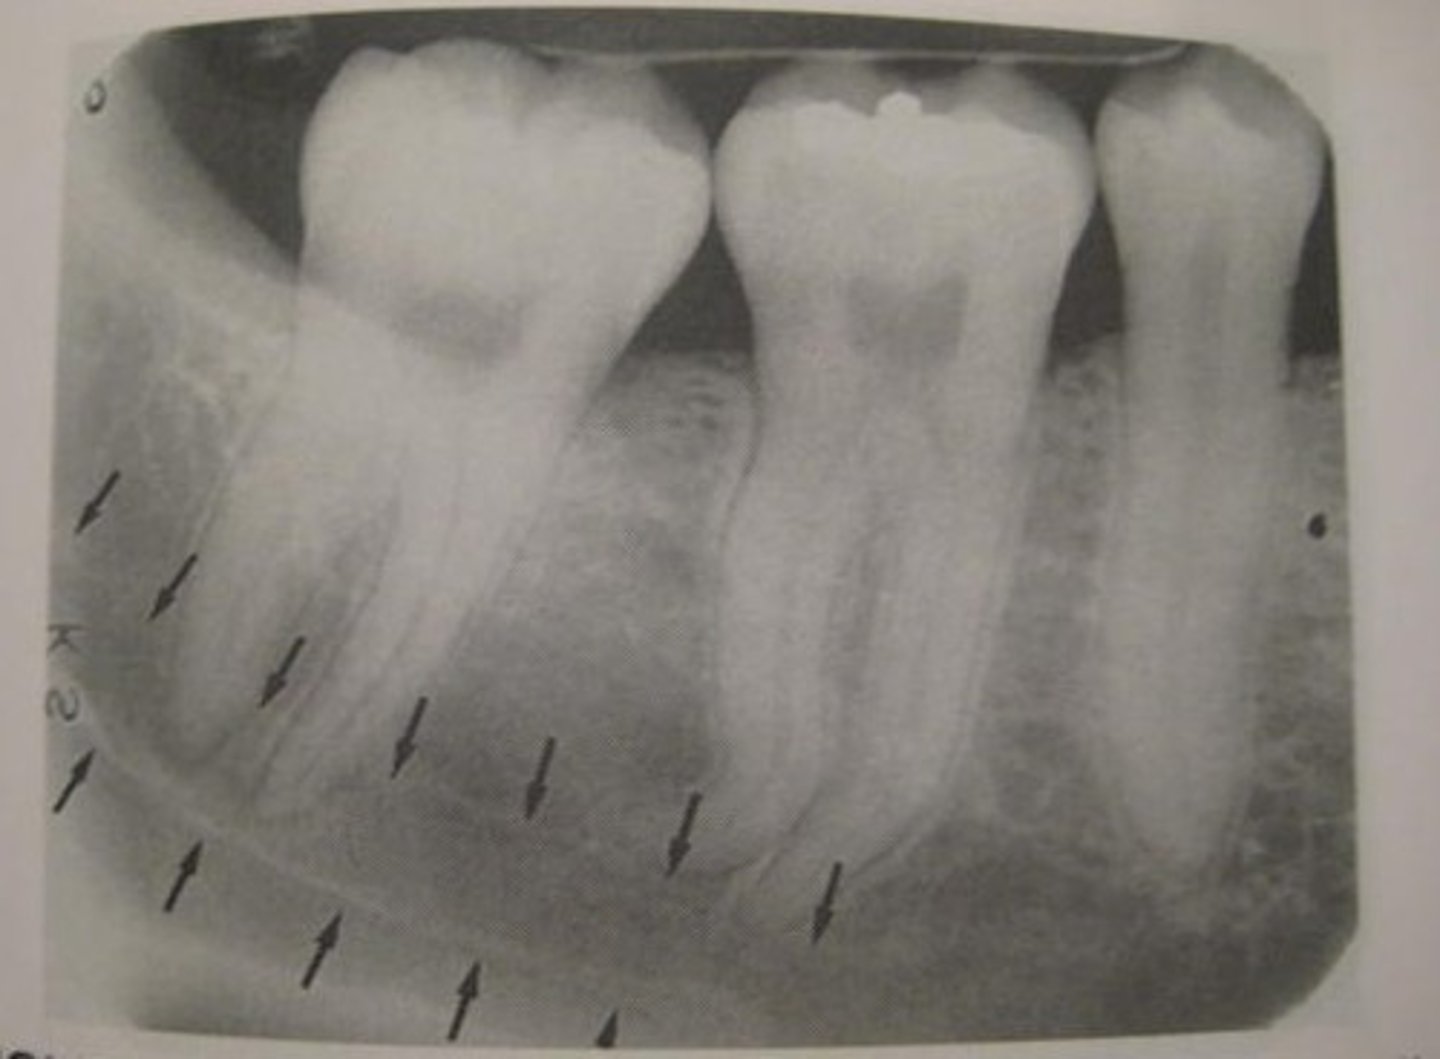

mandibular canal

border on top and bottom by a white line

passageway for nerves and blood vessels

submandibular gland fossa

rounded area of bone

less dense

space for submandibular salivary gland

mental foramen

hole between roots of premolars

mental ridge

runs from the premolar region to the midline of the mandible

prominence in bone forming chin